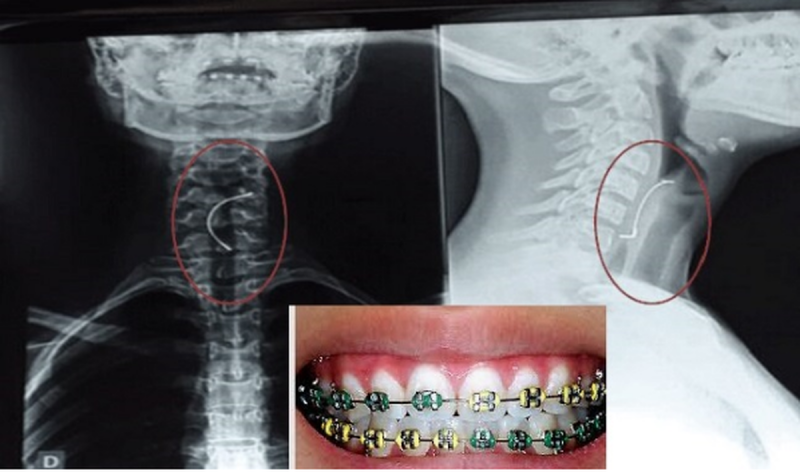

• Joven de 15 años se traga por accidente parte de sus brackets y casi muere

Joven de 15 años se traga por accidente parte de sus brackets y casi muere